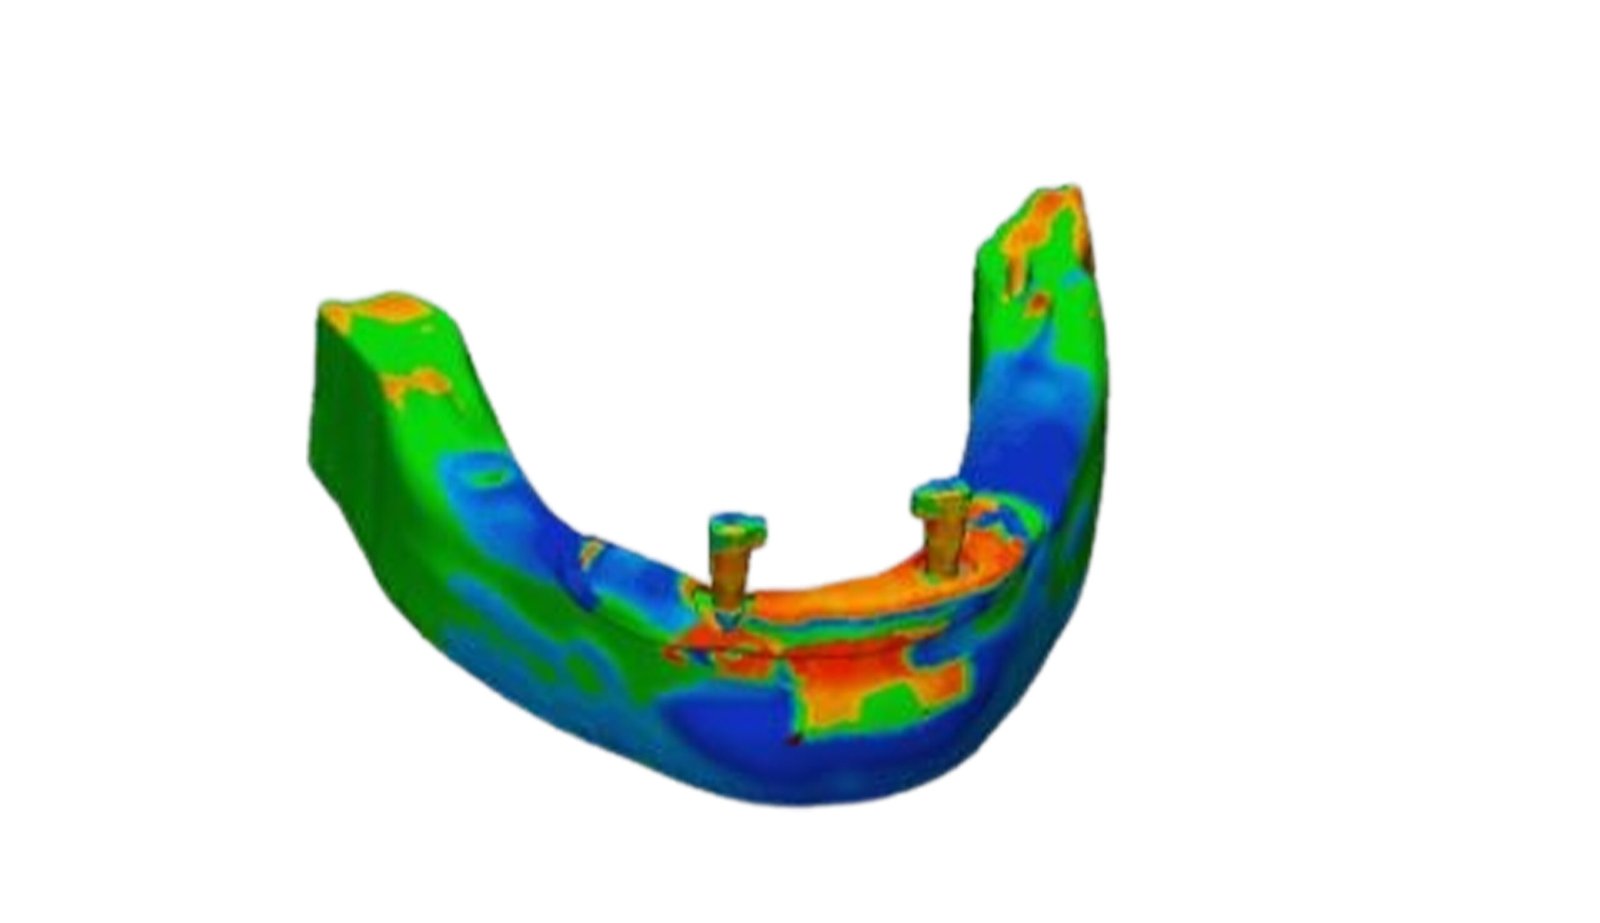

This section specializes in high-precision 3D deviation mapping to compare pre- and post-treatment anatomical or implant-related geometries. Using advanced superimposition and deviation algorithms, we quantify micro-level shifts, deformation zones, and structural discrepancies with sub-millimeter accuracy. These analyses support quality control, surgical verification, and design validation. The resulting deviation heat-maps provide clear, data-driven insights that enhance clinical decision-making and device optimization.